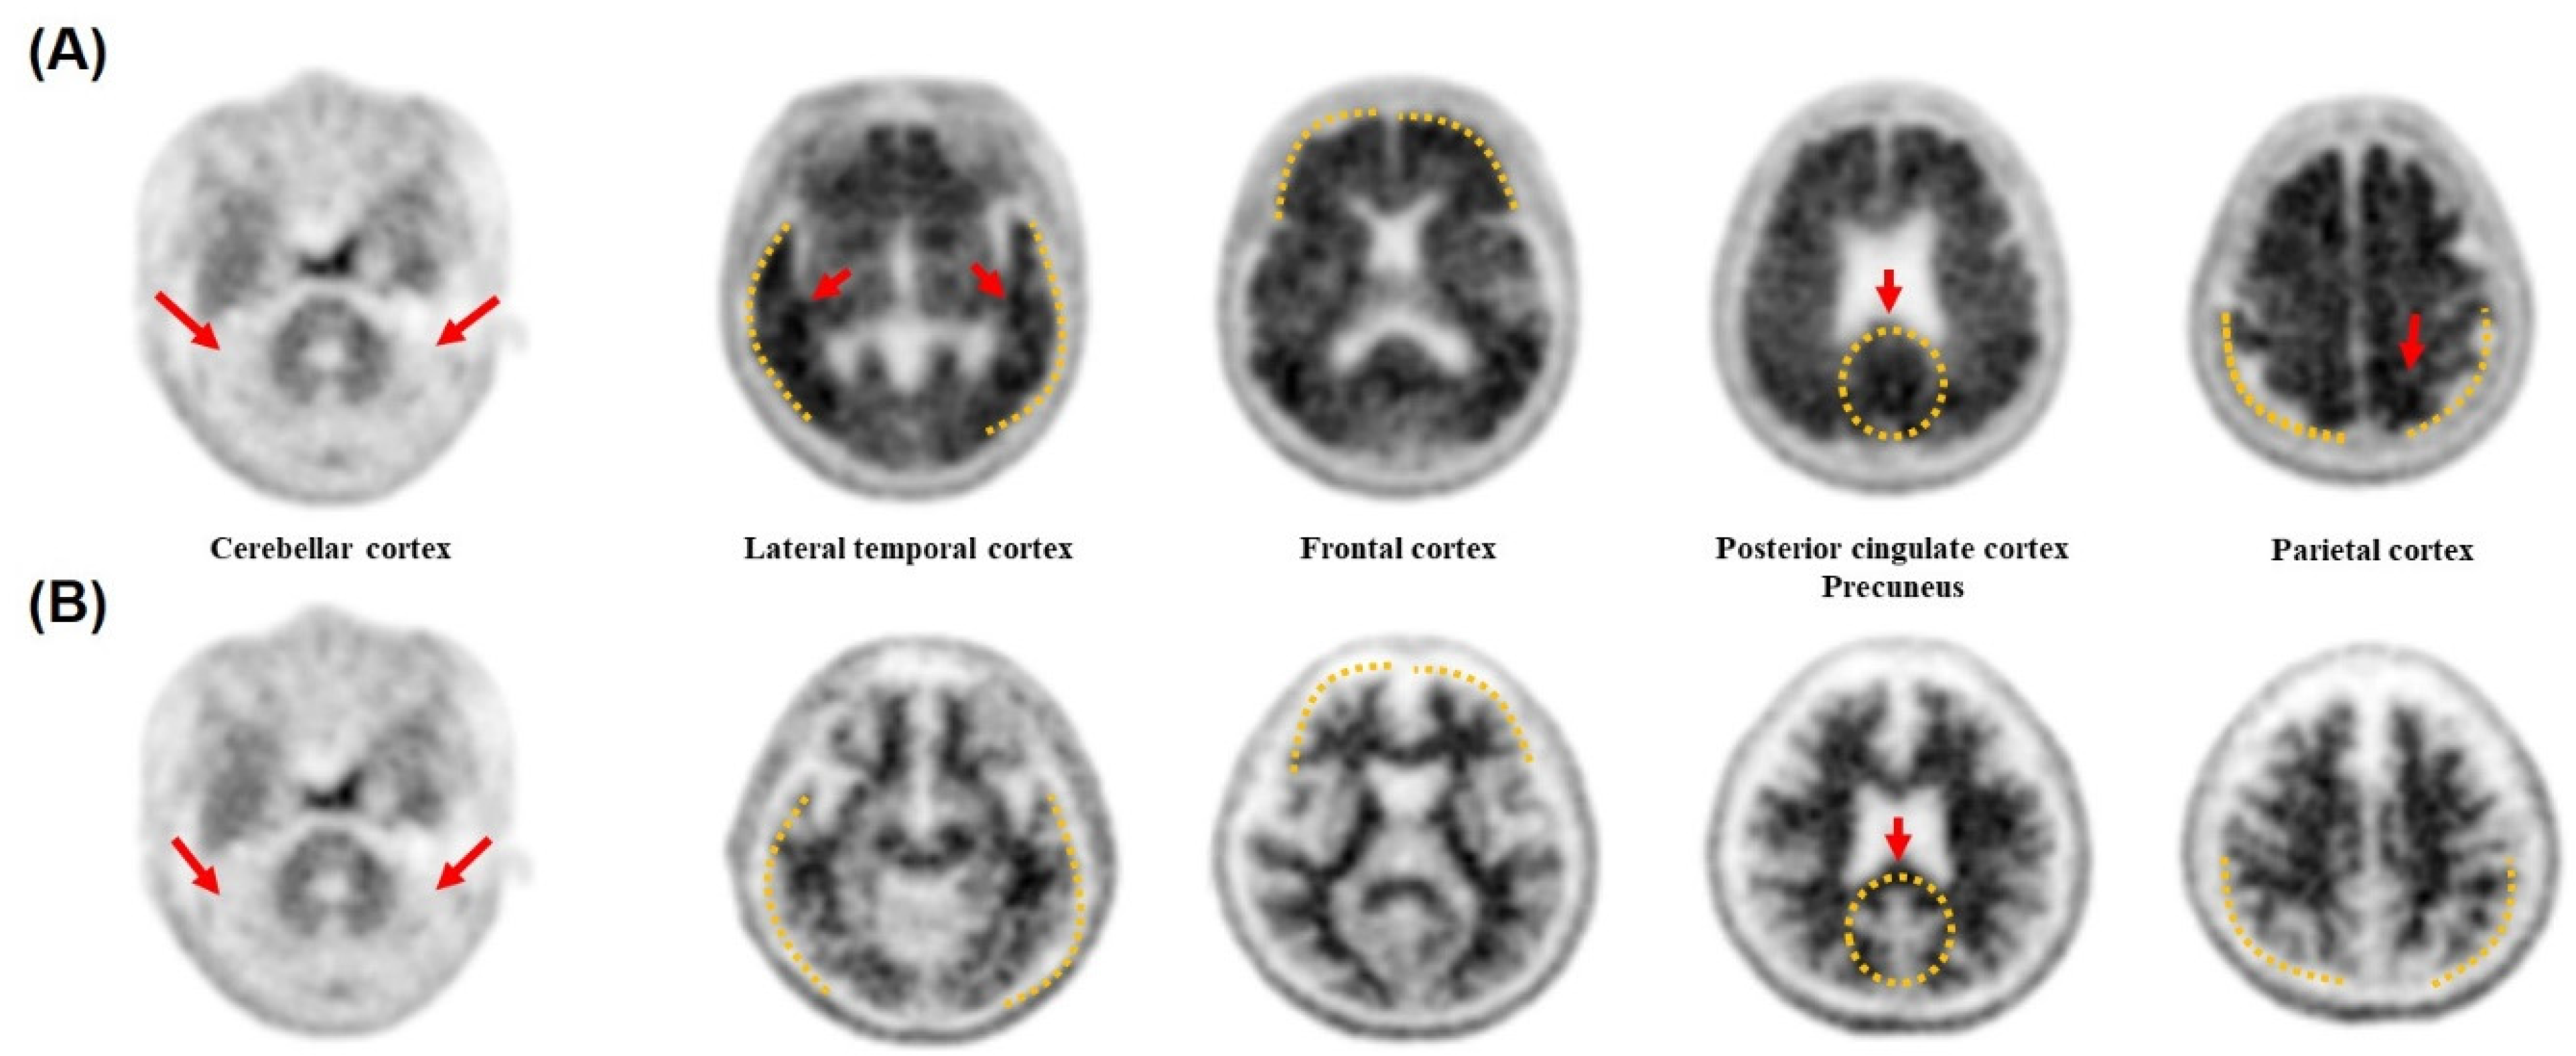

3.6. Accuracy Validation of the Diagnostic Methods by Cross Checking with the PET Images